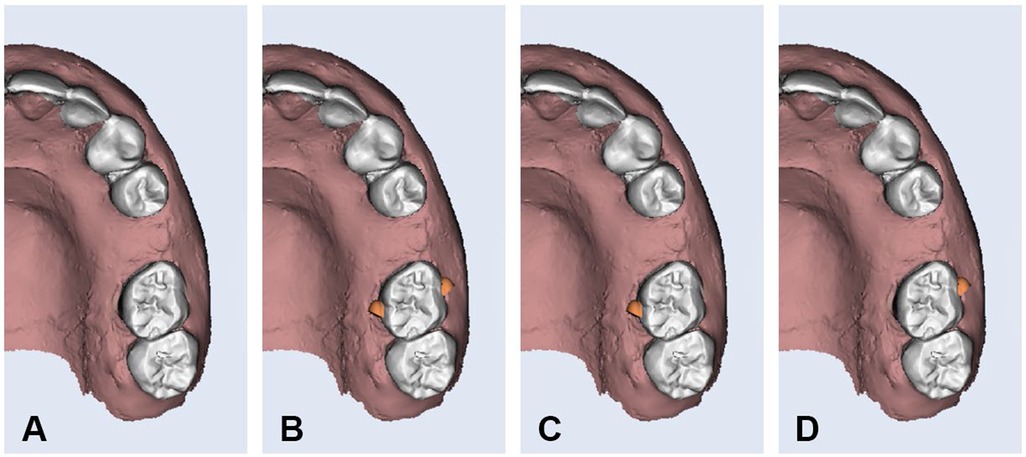

Aligners were manufactured with a thickness of 0.5 mm using Graphy Tera Harz TC-85DAC resin (Graphy Inc, Seoul, Korea), a shape memory polymer material that is designed for the production of clear aligners. Optimized attachments were designed with precise dimensions of 4 mm in width, 3 mm in height, and 2 mm in depth for all aligners in Groups 2, 3, and 4. A distal bevel was added to the design to facilitate the mesialization movement. Attachments were placed using the same attachment template in all groups (Figure 2). The attachment aligner interface remained intact in all specimens. Ten progressive aligners (Aligners 1–10) were digitally designed using standardized procedures. Each aligner was programmed to achieve an incremental mesial movement of 0.3 mm, resulting in a total of 3 mm of movement by the completion of Aligner 10. A baseline aligner (Aligner 0) was designed to establish and standardize the initial position of the maxillary left first molar at the beginning of each cycle.

Figure 2. Optimized attachment design on buccal and palatal surfaces of upper left first molar. (A) Group-1, (B) Group-2, (C) Group-3, and (D) Group-4.